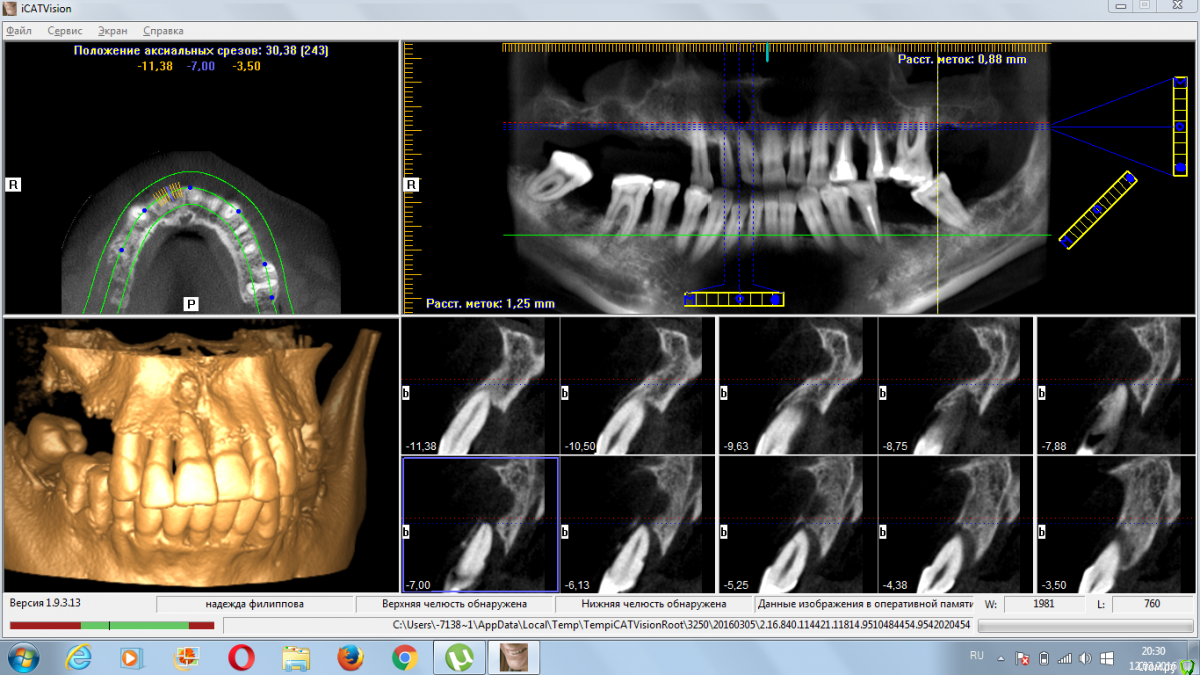

4ebstom Опубликовано 12 марта, 2016 Поделиться Опубликовано 12 марта, 2016 Коллеги,прошу помощи в плане лечения.36 лет,Ж.Не устраивает ЧСПП.Отмечает резкое расшатывание зубов.Соматику отрицает. Предварительно прикинул план лечения:1.Удаление2.Имплантация во всех сегментах.(синусы+нкр)3.Проф.чистка.Собственно вопросы:1.Как быть с утолщением слизистой пазух?Консультация ЛОР?2.Кюретаж открытый или?3.Как быть с протрузией?Ваши замечания и коррективы?Спасибо всем откликнувшимся. Ссылка на комментарий

Доктор Дмитрий Опубликовано 12 марта, 2016 Поделиться Опубликовано 12 марта, 2016 По поводу пазух- надо кт повыше сделать, скорее всего соустья свободные и оперировать можно. Вы сузили показания для удаления,по крайней мере на вч надо все удалять, даже если оставить 2,1 2,2 2,3 под временную опору- это ничего не даст. Импланты можно установить по шаблону. Можно обойтись без синусов, если по другому распланировать хирургию, например- все на 4. 1 Ссылка на комментарий

4ebstom Опубликовано 15 марта, 2016 Автор Поделиться Опубликовано 15 марта, 2016 Все на 4 х или 5 тоже меня вполне устроит.Сам склоняюсь к консолям на в.ч.Осталось объяснить пациенту расстаться с зубами. Ссылка на комментарий